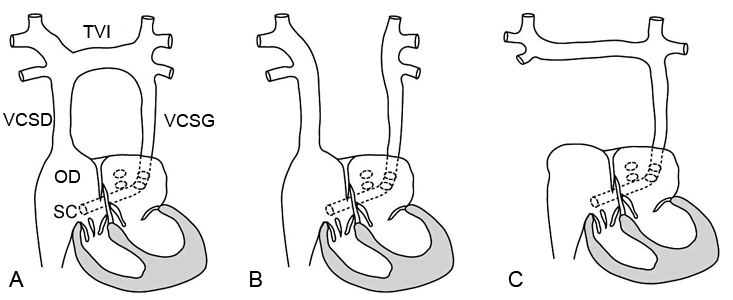

Les trois formes principales de veine cave supérieure double ou gauche sont représentées sur ce croquis (Kastler 2001 [1]). En A et B, correspondant à une veine cave supérieure double (environ 90% des cas), la veine cave supérieure droite se draine à la partie supérieure de l’oreillette droite et la veine cave supérieure gauche se draine dans le sinus coronaire (SC) en passant contre le bord gauche et en dessous du massif cardiaque. La seule différence entre ces deux variante porte sur l’existence ou non d’un tronc veineux inomminé (TVI) réunissant les retours veineux droit et gauches (absent dans 40% des cas).

Le cas d’une veine cave supérieure gauche unique, plus rare, est représenté en C.

D’autres variantes plus rares existent où la veine cave supéieure gauche se collecte dans l’oreillette gauche, ce qui entraine un shunt droite – gauche.